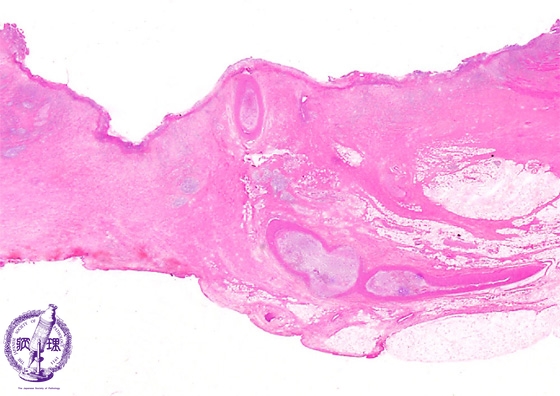

- ★(5)Peptic ulcer

Microscopic view (H&E stain, low power): The active ulcer penetrates into the serosa with serositis (dashed line). Within granulation tissue at the surface, an exposed artery (arrow) is observed.